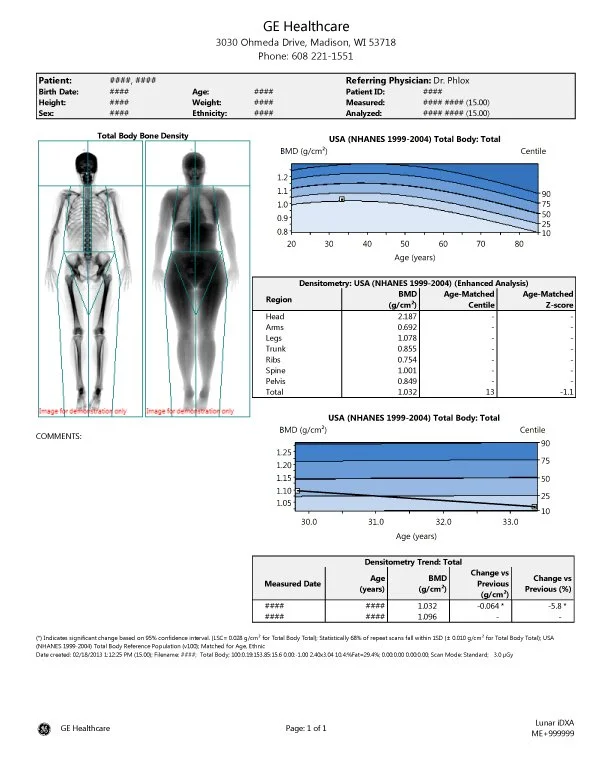

DEXA is the only widely used test that can accurately diagnose osteoporosis and osteopenia, and measure bone mineral density (BMD) over time.

For those concerned with bone health, specialized scans can be conducted that provide detailed analysis of key fracture-prone areas such as the spine and hip.